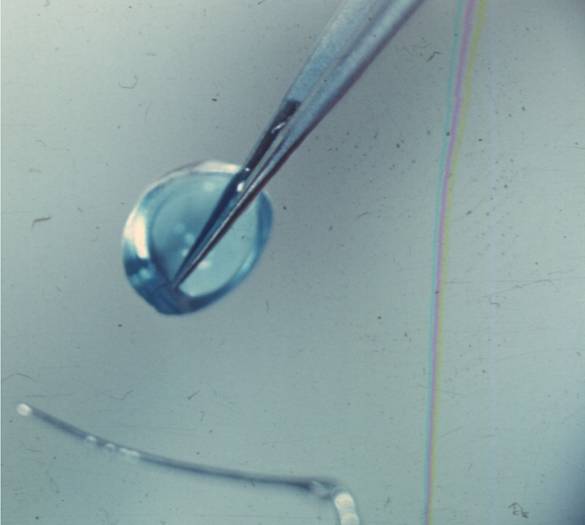

рис. 9.2.8), отмечая инъекционной иглой, смоченной 1% спиртовым раствором бриллиантовой зелени (см. рис. 9.2.9). Специальным отметчиком отмечают оптическую зону диаметром 6,0 мм (см. рис. 9.2.10). Сильный и слабый меридианы рефракции роговицы отмечают в области лимба перед подачей больного в операционную 1% спиртовым раствором бриллиантовой зелени по системе «Табо».С помощью отметчика роговицы (рис. 11.2.1) отмечают главные меридианы роговицы, затем определяют сектор сильного меридиана при простом миопическом астигматизме и по линии отметки оптической зоны производят насечку длиной до 1,0 мм на глубину 0,2 мм алмазным ножом с дозированной подачей лезвия, такую же насечку делают и в противоположном секторе (рис. 11.2.2) На глубине насечки специальным роговичным шпателем (рис. 11.2.3) делают расслаивание роговицы по линии отметки центральной зоны на % ее окружности. Точно такое же расслаивание проводят и в противоположном секторе. В сформированные тоннели микропинцетом вводят приготовленные заранее лентовидные трансплантаты с несколько заостренными краями и расправляют микрошпателем (рис. 11.2.4). Подсушенные трансплантаты имеют упругую консистенцию и легко вводятся в тоннели (рис. 11.2.5).

Лентовидные трансплантаты готовят методом параллельных сечений, описанных в разделе 8.2.1.

Для хирургической коррекции простого и смешанного астигматизма применяют трансплантаты следующих размеров:

■ от 1,5 до 2,5 дптр - 0,4 х 0,4 х 2,5 мм;

■ от 3,0 до 4,0 дптр - 0,4 х 0,5 х 2,5 мм;

■ от 4,5 до 5,0 дптр - 0,4 х 0,6 х 2,5 мм;

■ от 5,5 до 6,0 дптр - 0,4 х 0,7 х 2,5 мм.